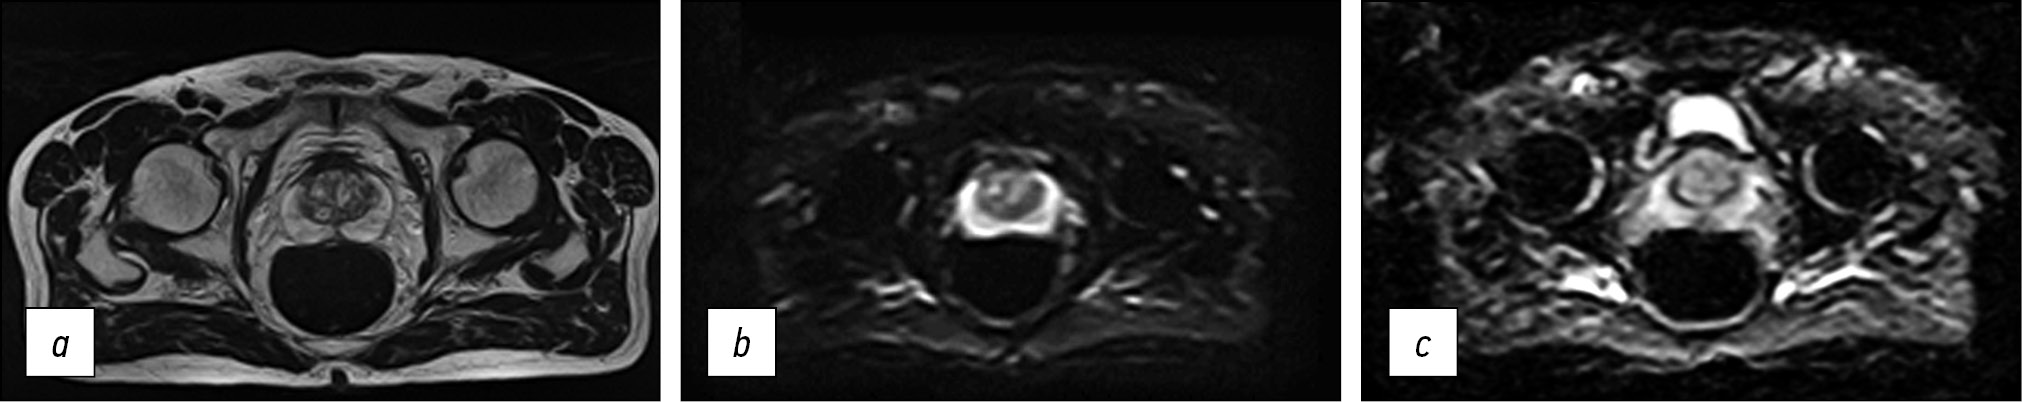

Fig. 4. Medical organization 3 (MO 3). In the peripheral zone on the left, a hypointense lesion on T2-WI and ICD map is defined (arrows): a) T2-WI, axial projection (TR 5082, TE 75, FOV 40×30 cm, Matrix 512×256); b, c) DWI and ICD (TR 8841, TE 100, FOV 30×30 cm, Matrix 128×128).

Note. Here and in Figures 3–5: T2-WI, T2 weighted images; DWI, diffusion-weighted images; MDC, measured diffusion coefficient; TR, repetition time; TE, echo time; FOV, field of view; Matrix is a matrix.

Thus, in all presented HO MHD, the requirements recommended by PI-RADS v2.1 for the presence of T2-WI in the axial and at least one additional (sagittal and/or coronal) views were met. In addition, it should be noted that the recommended layer thickness for T2-WI in the axial view should be no more than 3 mm, while in HO 2 and HO 3, it is 4 mm (Figures 3 and 4). The same is true for HO 1, where the DWI slice thickness is 5 mm with the recommended 4 mm or less (Figure 2). An important factor is the field of view; according to PI-RADS v2.1, field of view (FOV) values for T2-WI should be 12–20 cm, while in HO 1 and HO 3, the field of view is much larger (30 × 35 cm and 40 × 30 cm, respectively) (Figures 2 and 4). According to PI-RADS v2.1, the recommended field of view for DWI is 16–22 cm, although none of the three HOs adhere to this standard. The fact of the variability of the FOV values and the section slice thickness inevitably affects the resolution and, as a result, the ability to detect lesions.